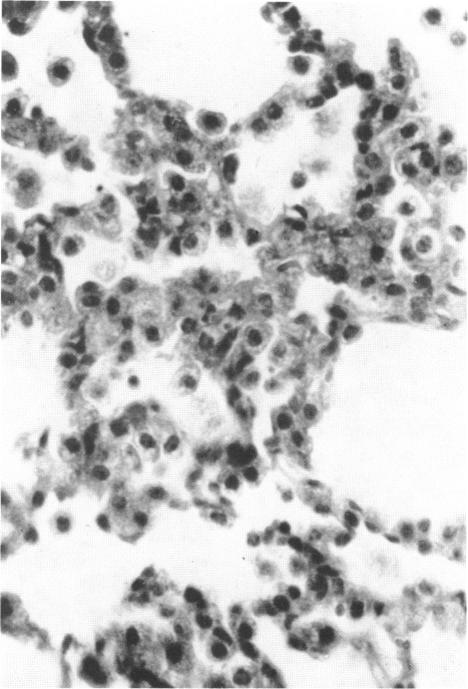

Neoplastic and nonneoplastic effects of vinyl chloride in mouse lung

Source:Environ Health Perspect. 41:31-52.